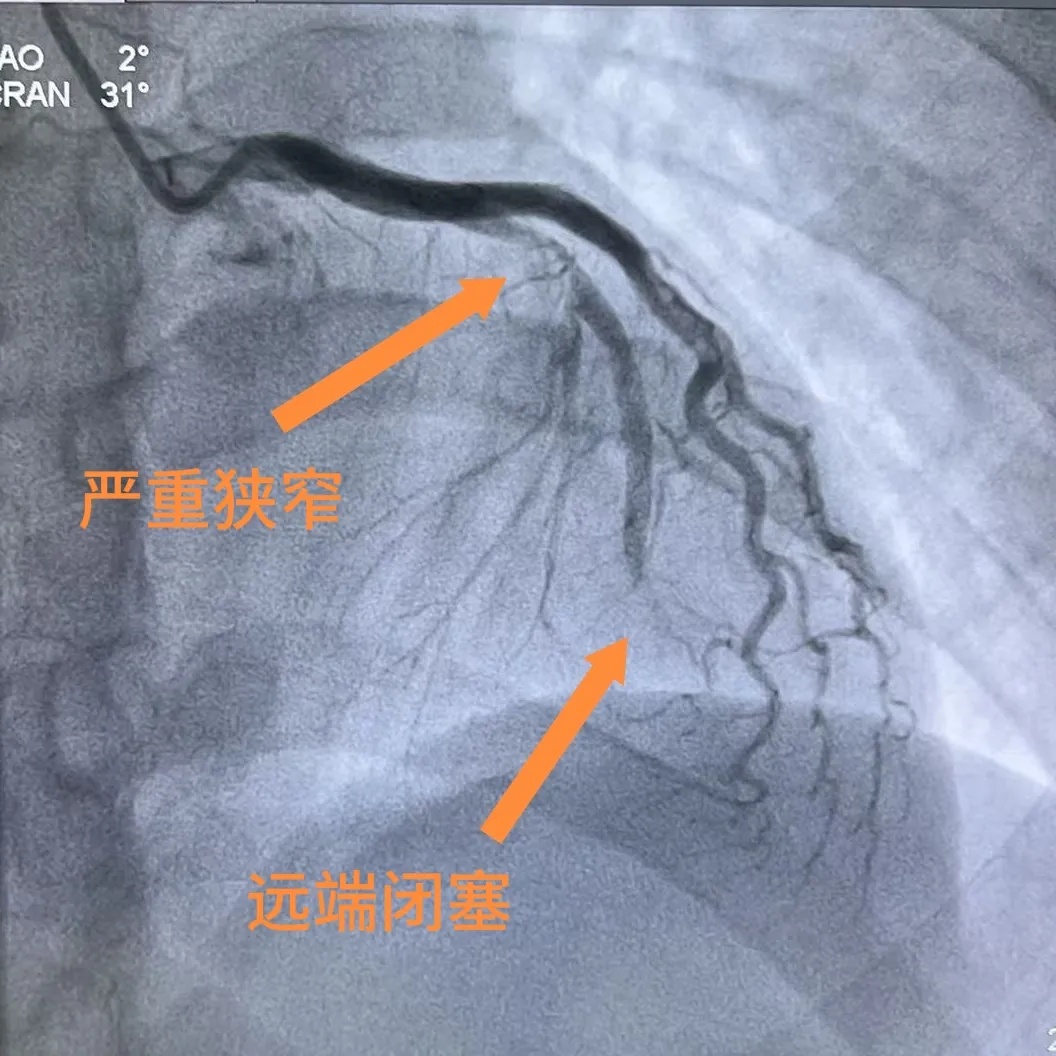

术前造影

玉环二医胸痛中心立即启动绿色通道,林先生急诊冠脉造影结果令人惊心:心脏供血的关键血管——左前降支近中段狭窄高达90%,远端已完全闭塞,血管内堵塞着大量血栓,随时可能引发心脏骤停,危及生命。